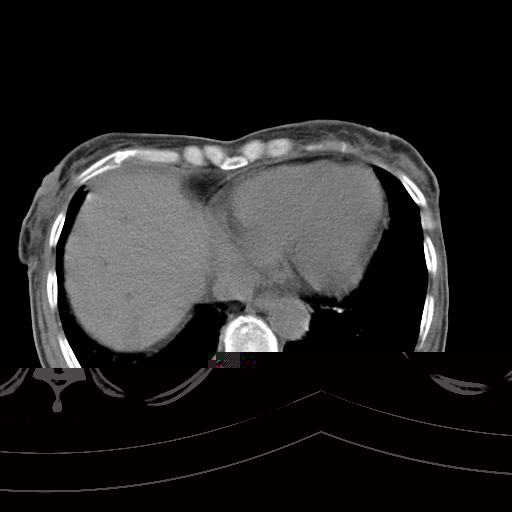

病人上腹部胀痛拌全身黄染八天

右侧胸腔少量积液,右下叶结节灶,。

1)考虑胰头癌并胆系低位梗阻;建议行ct增强扫描检查。2)慢性胆囊炎。3)脾大。4)少量腹水。5)双侧少量胸腔积液。